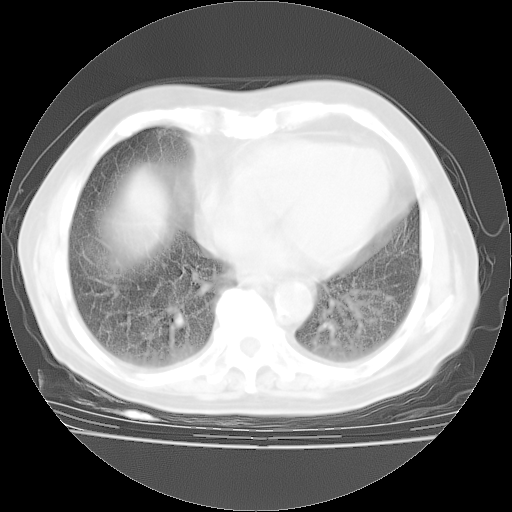

今天部分检查

轻微咳嗽,无痰,(体温正常时)R20次/分,P75次/分,双肺底、腋下可闻及少量捻发音。下肢轻度浮肿。